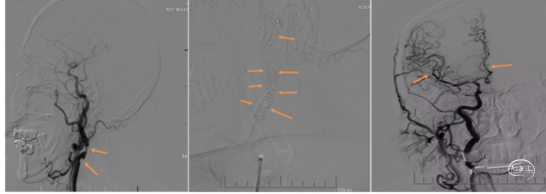

术前CTA

手术过程

1、行右侧股动脉穿刺并置入8F动脉鞘成功。造影发现左侧大脑中动脉M3段以

远显影欠佳。正位不清晰,斜位清晰可见M3闭塞。

2、5F 125cm 中间导管抽吸:

泥鳅导丝引导8F导引导管至左侧颈内动脉C1远端平直处建立通路,微导丝引导微导管及5F 125cm 中间导管到达左侧大脑中动脉M3闭塞段近端。

近端使用60mL注射器手动抽吸两次,未见血栓取出。可能为导管未能接触血栓。

注意: 6F 125cm 中间导管到达大脑中动脉M1段; 5F 125cm中间导管到达大脑中动脉M2分叉以远。

3、换用3MAX 抽吸导管通路组合:

8F MPA+3MAX抽吸导管+微导丝,抽吸两次后栓子逃逸至远端分叉部。

5、 再次跟进3MAX抽吸一次,完全再通。

术后即刻复查XperCT未见出血。